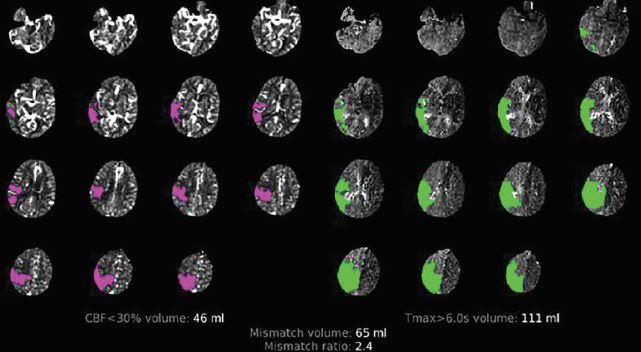

CT perfusion:

Assess the core and the penumbra (brain at risk)

Core features: increased MTT, markedly decreased CBF and CBV

Penumbra features: increased MTT, moderately reduced CBF, normal/increased CBV

More likely to have favourable outcome with mismatch ratio >/= 1.8, volume >/= 15mL

Click image to enlarge

[Source: Dr. Phavalan Rajendram Emergency Lecture 2020]